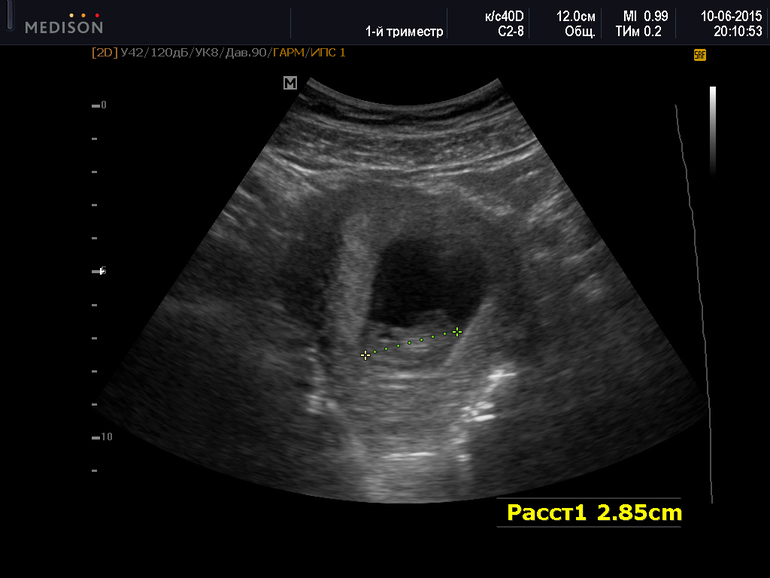

Очередное УЗИ( 10 недель)

Сходили вчера на внеплановое УЗИ. Я хотела убедиться, что с детенышем все ок, прежде, чем рассказывать родителям. На УЗИ все ок, подросли до 2, 85 см. Миша наконец-то попал на УЗИ, посмотрел, послушал сердечко) Правда на картинке особо ничего не понял, говорит) Я ржу) Говорю, что через месяцев 7 точно все поймешь)))))

На предыдущем УЗИ по КТР ставили срок на 2 меньше, чем по месячным, а нынче даже обогнали на 1 день:) Остался тонус по левой стенке, надеюсь к следующему УЗИ все будет ок. Тонус в общем то не удивителен, учитывая, что у нас в разгаре переезд. Я тяжелые коробки, конечно, не таскаю, но какую-то мелочь туда-сюда пока перенесешь, пока нагнешься-разогнешься, вот тонус и вылез наверное...

Под катом фото с УЗИ) Не пойму где голова, а где жопа:))))